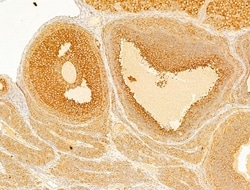

| Immunocytochemistry, Immunohistochemistry (Paraffin), Western Blot | |